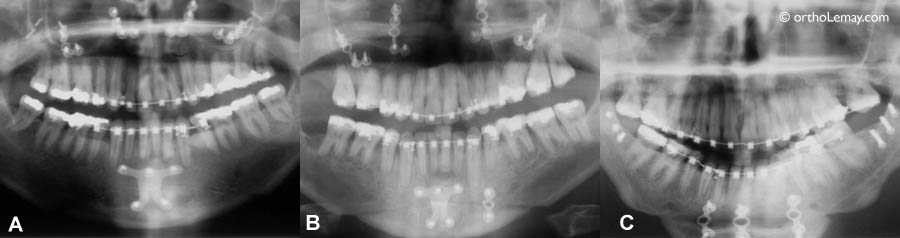

(A) Garçon de 12 ans traité en orthodontie pendant une période de croissance ce qui a permis d’améliorer la relation des mâchoires (B) Résultat après 14 mois. Sans croissance une chirurgie est nécessaire chez l’adulte pour corriger un tel déséquilibre d’où l’importance d’un suivi et intervention précoces pendant la croissance et le développement de l’enfant.